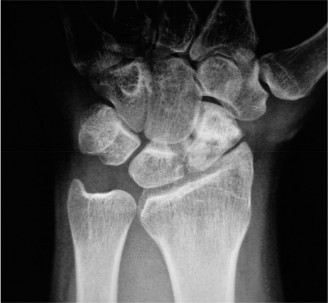

CASE 11 ### A patient presents to your clinic with ulnar-sided wrist pain. X-ray is as shown in Figure 3–10. What is your diagnosis?

Figure 3–10(©) Sunil Thirkannad and Christine M. Kleinert.

The correct answer is (D). The findings in the radiographs are consistent with pisotriquetral arthritis.